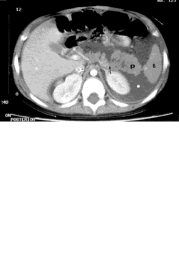

Cavidades no revestidas de epitelio que contienen sangre, pus y jugo pancreático

-Persisten 4 a 6 semanas luego de un episodio de PA

Seudoquistes